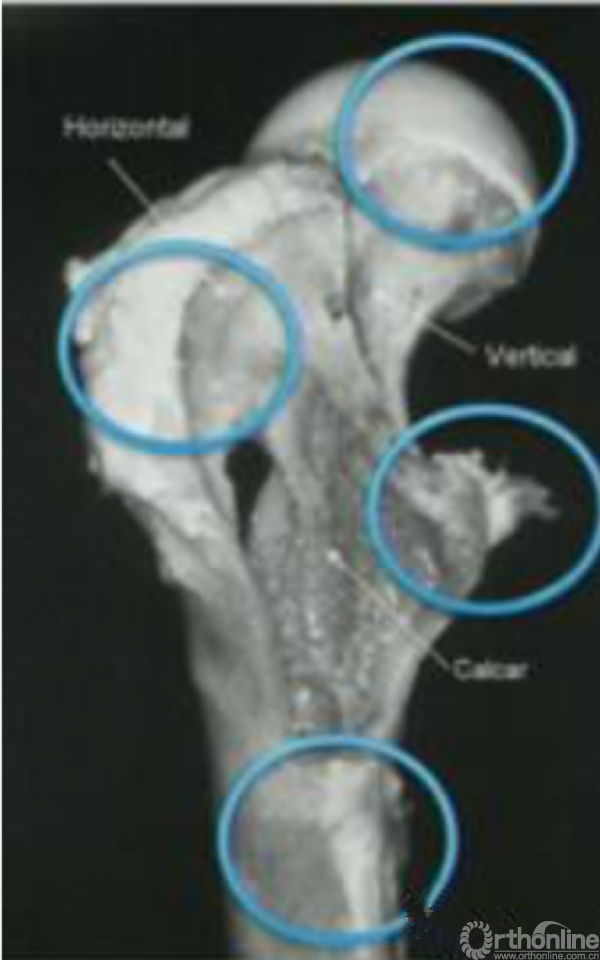

股骨近端生物力学坚强吗?一点也不...我们先来看一下股骨近端的解剖学研究,股骨近端承受身体巨大的重量,但股骨近端中却有三个骨量缺失的地方。

股骨近端有四个重要的组成部分,大粗隆,小粗隆,股骨头,股骨干。其中有一个重要的生物力学传导,股骨距也是股骨近端后内侧的重要稳定结构。

随着年龄的增加,股骨出现骨质疏松,前后的皮质开始变薄。此时出现骨折的风险逐渐增加。